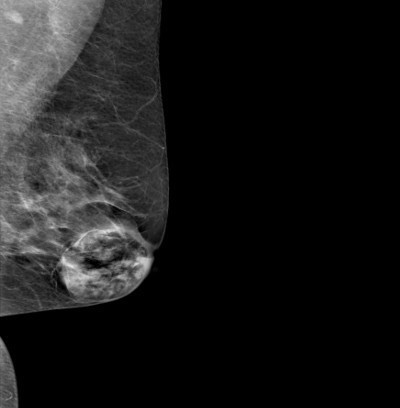

👉They are round, oval, or lobulated and are usually well-circumscribed.

👉They have a mixture of water density and fatty elements and frequently have either a capsule or the appearance of a capsule resulting from surrounding compressed breast tissue.

👉A mammographically classic hamartoma does not require further imaging, short interval follow-up, or biopsy.